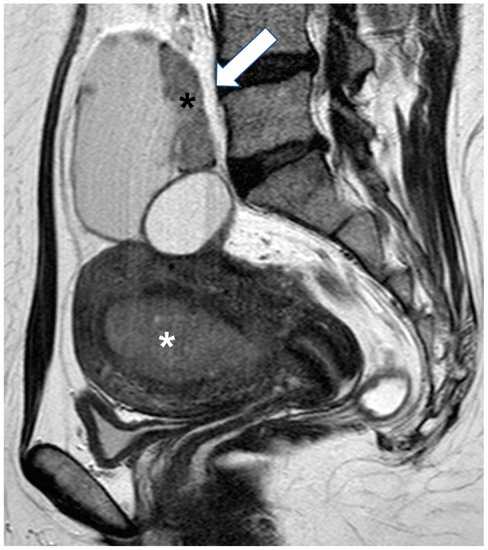

2.5.2. Decidualized Endometrioma

2.5.3. Epithelial Ovarian Cancer